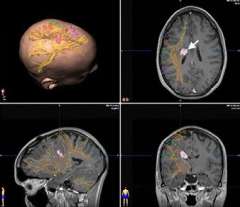

Diffusion Tensor Imaging (DTI): White matter contains the cabling (axons) connecting one part of the brain to another. In the case of the motor system, cutting the cables (corticospinal tract) will result in paralysis. This set of DTI images shows how close the corticospinal tracts (arrow, lower left image) are to the tumor (yellow). Standard MRI imaging does not show this information. UCLA neurosurgeons routinely use this information.

The upper left image is a three dimensional view of the head with the tumor shown in purple and the white matter tracts (identified by DTI) in yellow. The other images show the same information in three different cross sections through the brain (tumor shown by arrow).